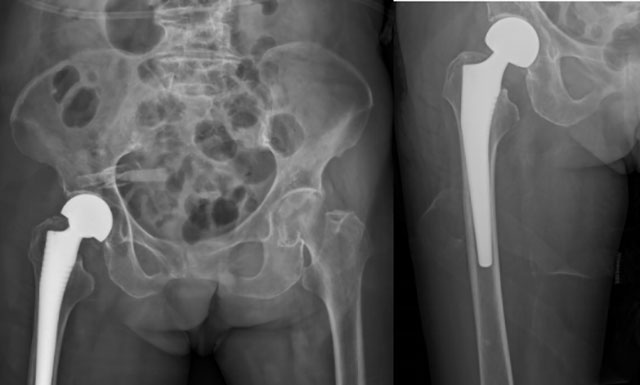

在制定了周密的手术方案和应急预案后,骨科团队凭借精湛的技术,成功为杨婆婆实施了“半髋关节置换术”。手术时间短、创伤小、出血少,为术后的快速康复打下了基础。“双侧胸腔闭式引流术+心肺康复”有效缓解了婆婆呼吸困难,控制肺部感染。